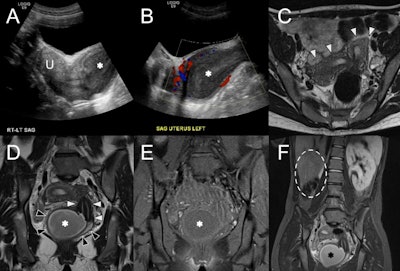

OHVIRA syndrome. (A) Sagittal ultrasound image at the level of the uterus (U) shows echogenic contents distending the vagina (asterisk) with (B) no color Doppler flow. (C) Axial T2w MRI shows two widely splayed uterine horns (white arrowheads). (D) Coronal T2w MRI demonstrates two separate cervices (white arrowheads) and vaginal cavities (black arrowheads) consistent with uterine didelphys. The right hemivagina is distended with fluid (asterisk), consistent with obstruction. (E) Coronal fat-suppressed T1w MRI at the same level shows low signal intensity of the vaginal contents (asterisk), suggestive of hydrocolpos. (F) Wide field-of-view fat-suppressed T2w MRI shows right renal agenesis (dashed line) ipsilateral to the side of vaginal obstruction (asterisk). All figures courtesy of Dr. Monish Ahluwalia, Dr. Andrew Chung, and EJR.

“Transabdominal and transvaginal ultrasound is the first-line imaging modality, which demonstrates uterine didelphys, echogenic hematocolpos or hematometrocolpos, and unilateral renal agenesis. There should be no colour Doppler flow in the vaginal contents to differentiate from a vascular mass. Care should be taken to appropriately delineate anatomic structures, as hematocolpos can be mistaken for a pelvic abscess or endometrioma,” the authors pointed out.

MRI allows for detailed delineation of uterine morphology and the continuity of each vaginal channel, in addition to the findings on ultrasound. Low signal on T1-weighted imaging (T1-WI) suggests hydrocolpos, while high signal indicates blood contents. CT may show similar findings, albeit with lower contrast resolution.